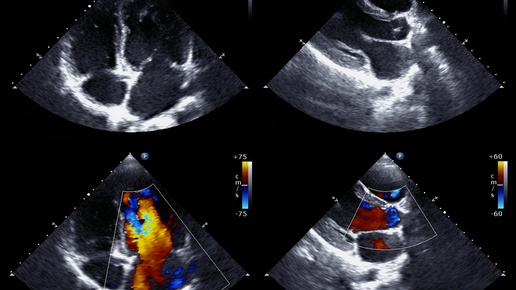

Всех приветствую на своем канале! Я врач из Челябинска. Эхокардиография (ЭхоКГ, УЗИ сердца) — это современный, безопасный и неинвазивный метод диагностики заболеваний сердца с помощью ультразвука. Он позволяет врачу получить подробную информацию о структуре и работе сердечной мышцы, клапанов, камер сердца и крупных сосудов. В этой статье расскажу о том, что такое эхокардиография, какие виды исследования существуют и кому оно показано. Эхокардиография представляет собой ультразвуковое исследование сердца...

Кто проводит эхо-тест? Какие методы используются? Какие виды бывают? Сколько времени занимает? Когда мне понадобится эхокардиограмма? Что показывает эхокардиограмма? Что такое эхокардиограмма? Эхокардиограмма (эхо) представляет собой графическую схему движения вашего сердца. Во время эхо-теста ваш лечащий врач использует ультразвук (высокочастотные звуковые волны) из ручного датчика, помещенного на вашу грудь, чтобы сделать снимки клапанов и камер вашего сердца. Это помогает врачу оценить насосную функцию вашего сердца...